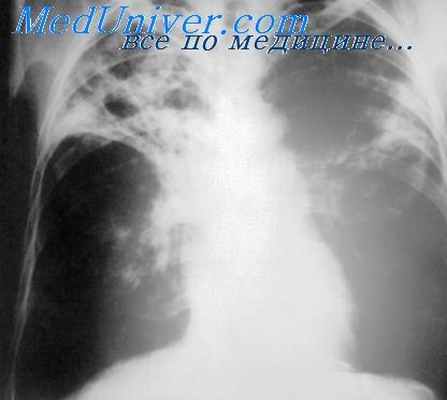

Несостоятельность культи бронха – осложнение лоб-, билоб- или пульмонэктомии, представляющее собой дефект швов, наложенных на культю, и обеспечивающее прохождение воздуха в плевральную полость, экссудата – в бронхи и трахею. Проявляется болями на стороне операции, кашлем с обильным отделением кровянистой жидкости, одышкой, лихорадкой, подкожной эмфиземой. Диагностируется на основании клиники, данных лучевых методов исследования лёгких, бронхоскопии. Для закрытия дефекта культи выполняется бронхоскопия с электрохимической коагуляцией или реторакотомия с торакопластикой или реампутацией бронха.

- Рентгенографии, КТ грудной полости. В раннем послеоперационном периоде на рентгенограмме и компьютерных томограммах можно обнаружить смещение или отсутствие танталовых скоб, применяющихся при механическом сшивании раны. Позднее появляются признаки пневмоторакса, гидроторакса с горизонтальным уровнем. Для уточнения локализации отверстия иногда используется бронхография.